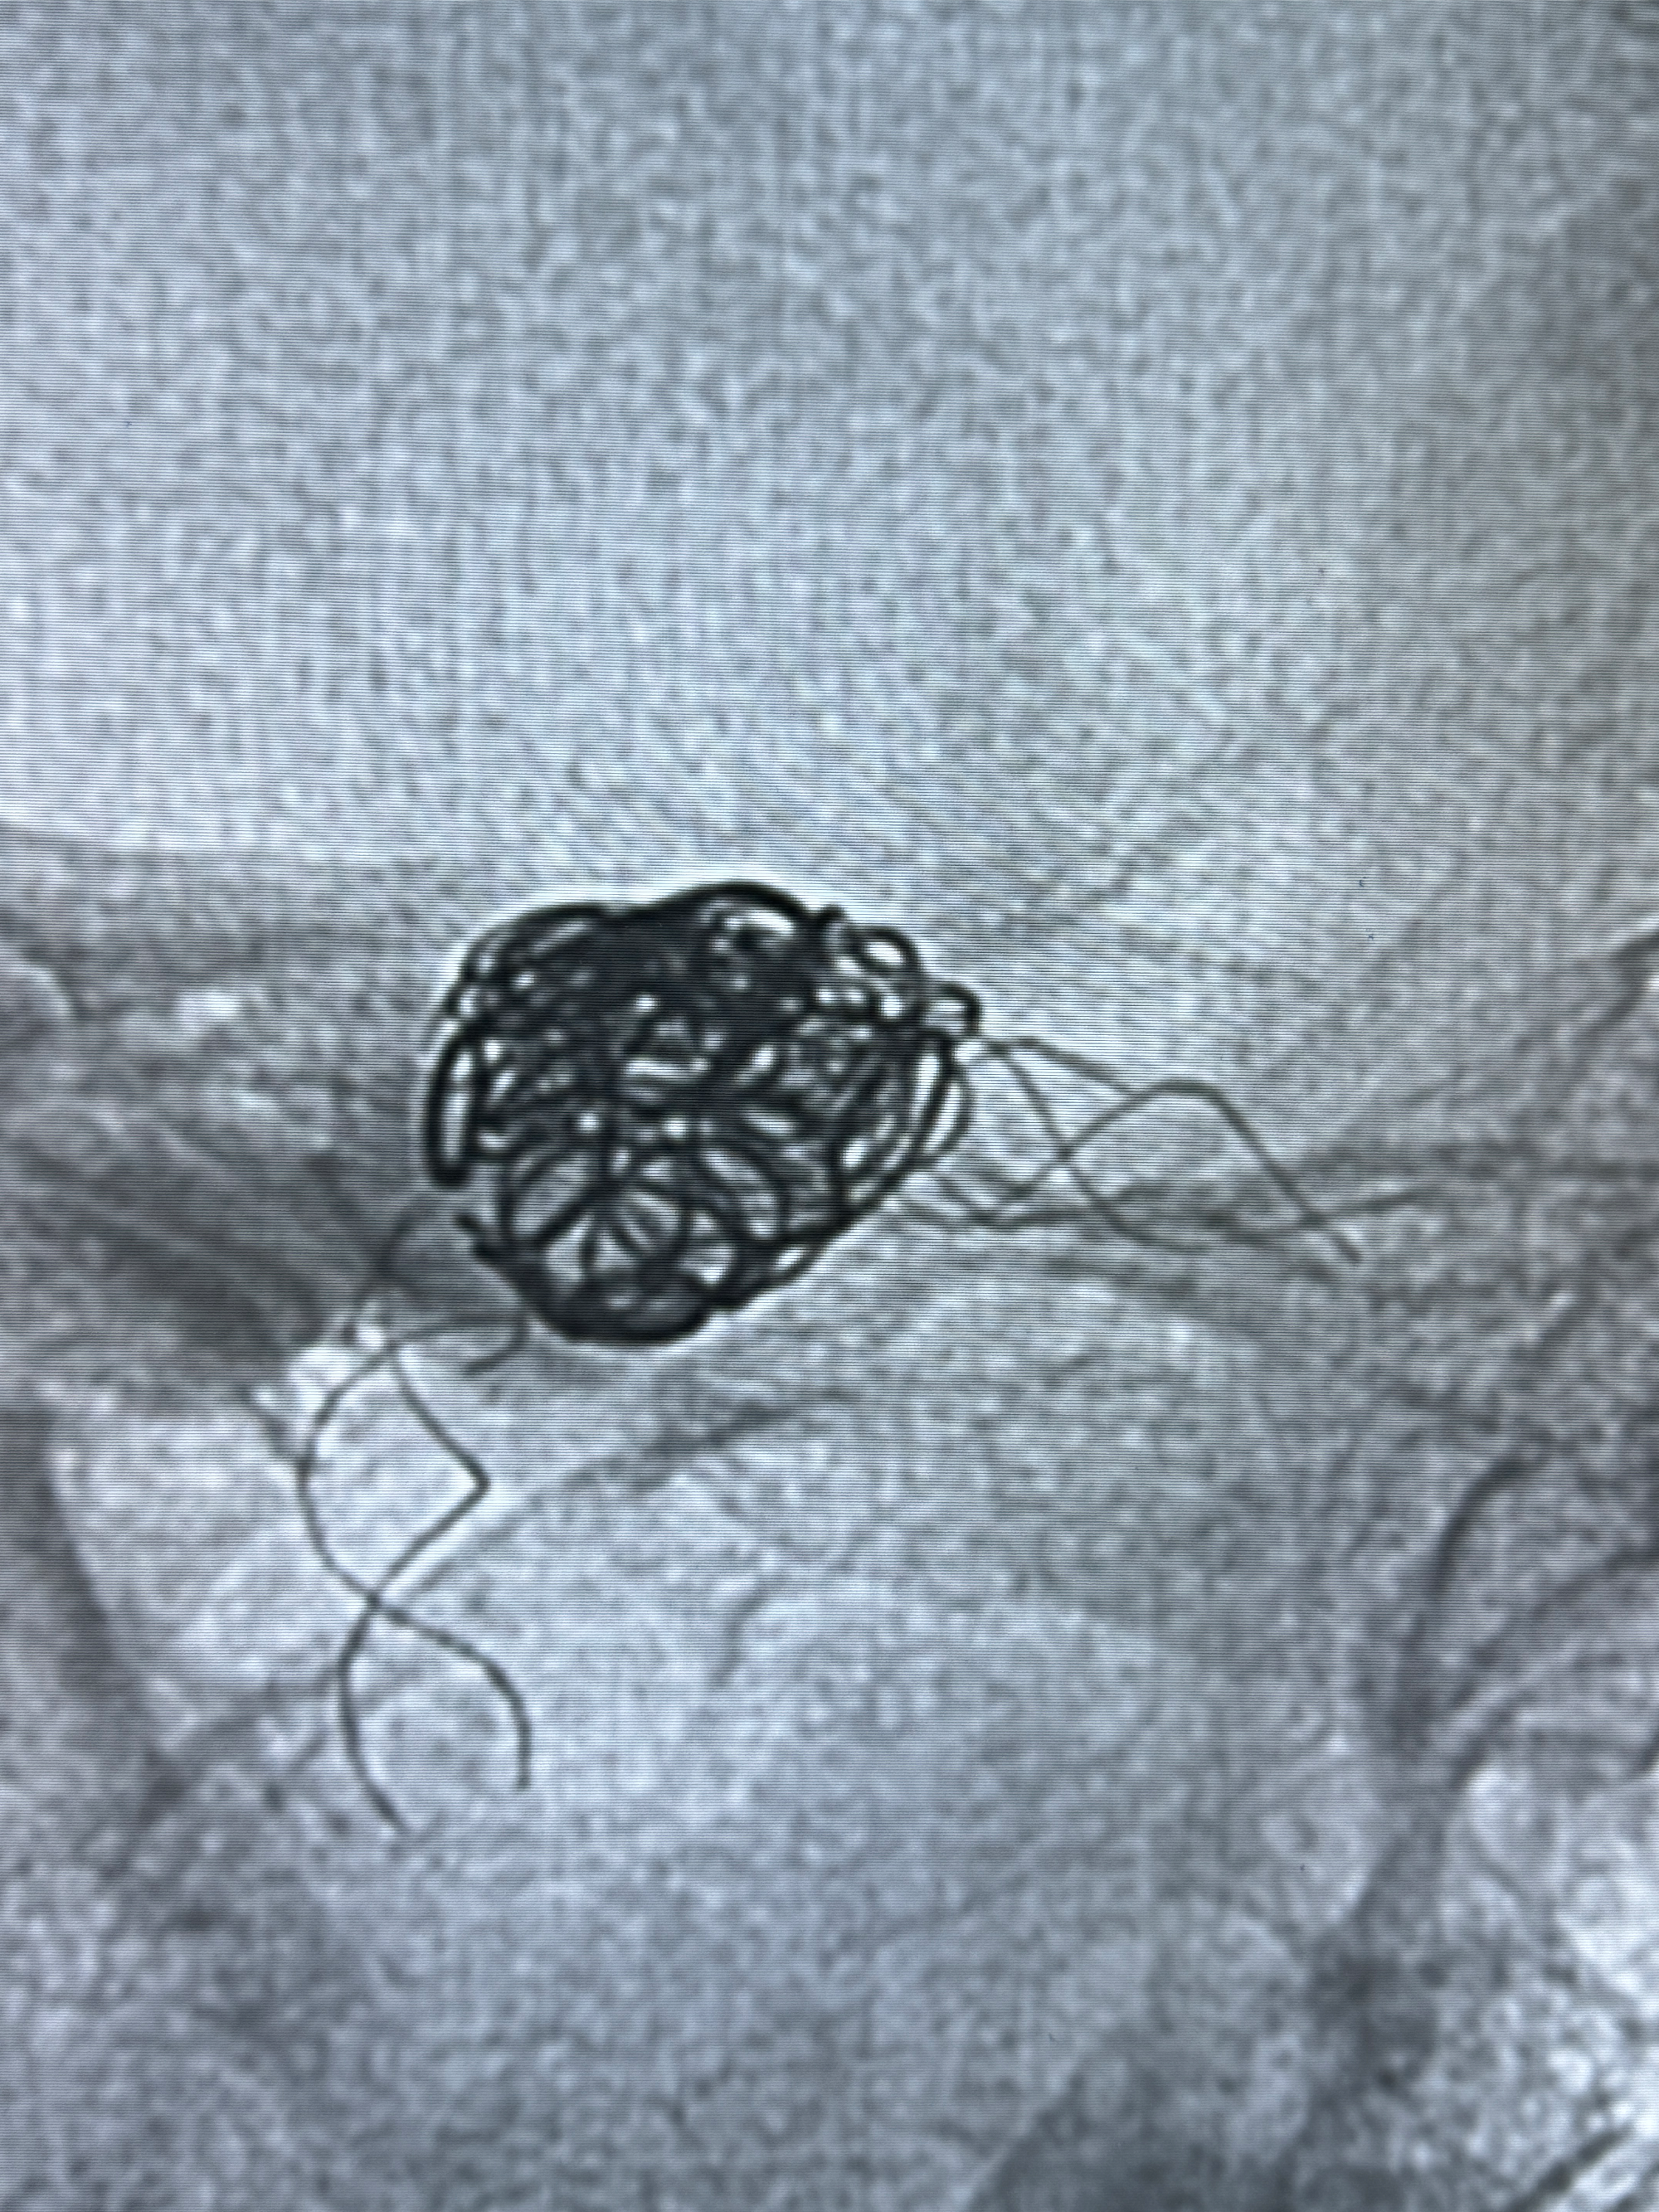

2024-01-08DSA:右侧椎动脉V4段夹层动脉瘤双支架辅助弹簧圈栓塞术后

患者支架辅助治疗后18个月,动脉瘤痊愈